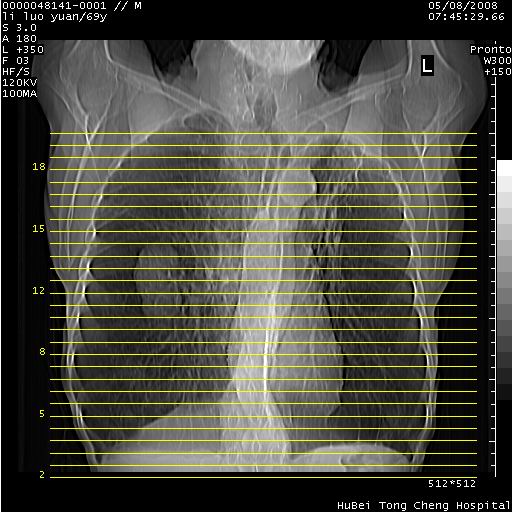

临床资料:老年患者,咯血、消瘦

影像表现:桶状胸,双肺纹理纤细、紊乱,透过度增高,肺野内可见多发、散在、大小不等的无壁高透过影,右肺中叶外侧段分叶样软组织占位,左上肺纤维索条样密度影,相应层面左侧胸腔轻度萎陷,纵隔左移。

影像诊断:1、慢支、肺气肿、双下肺野肺大泡形成

2、左上肺陈旧性肺结核

3、右肺中叶外侧段占位 考虑肺ca可能性较大、建议增强及痰检脱落细胞